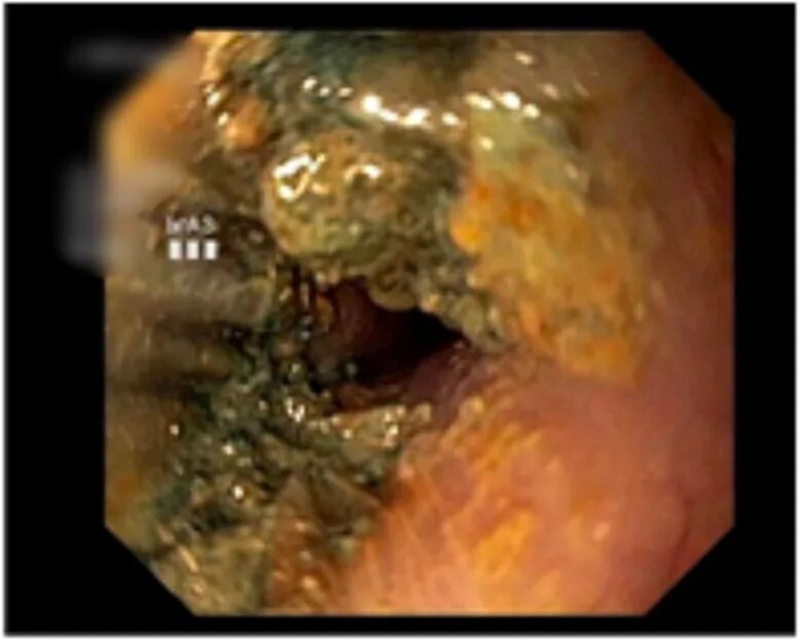

軒軒的遭遇并非個例。在兒科診室里,類似的消化道異物傷害案例屢見不鮮。

醫(yī)院近期取出的消化道異物

其中,3歲以下幼兒更是高危群體。這個年齡段的孩子好奇心旺盛,習(xí)慣用嘴巴探索世界,且吞咽反射尚未發(fā)育完全,像紐扣電池、磁力珠、堅果這類不起眼的小物件,一旦被誤吞,很可能造成不可逆的嚴重傷害。軒軒的遭遇,也再次給廣大家長敲響了安全的警鐘:做好防護,讓孩子遠離這類潛在傷害。